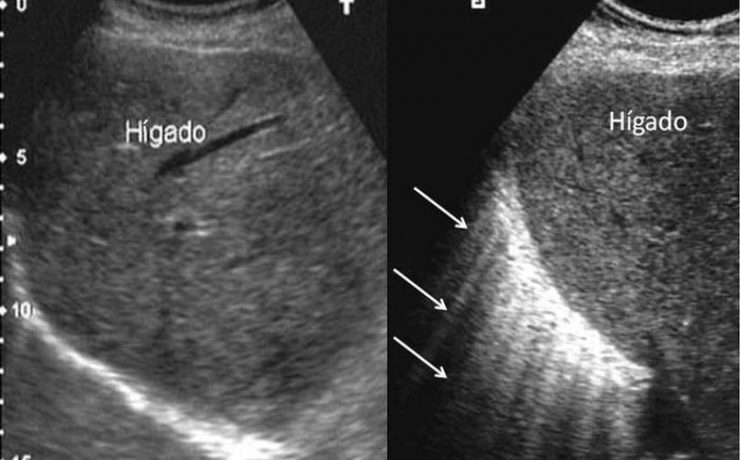

La ecografía transvaginal es el gold-estandar para la evaluación de la patología ginecológica estructura tanto benigna como maligna, con óptimo rendimiento. Actualmente la anatomía patológica funcional no forma parte del estudio ultrasonografico de rutina. Lo que lleva a un sub diagnóstico de patologías frecuentes, como por ejemplo: metrorragias o amenorreas.